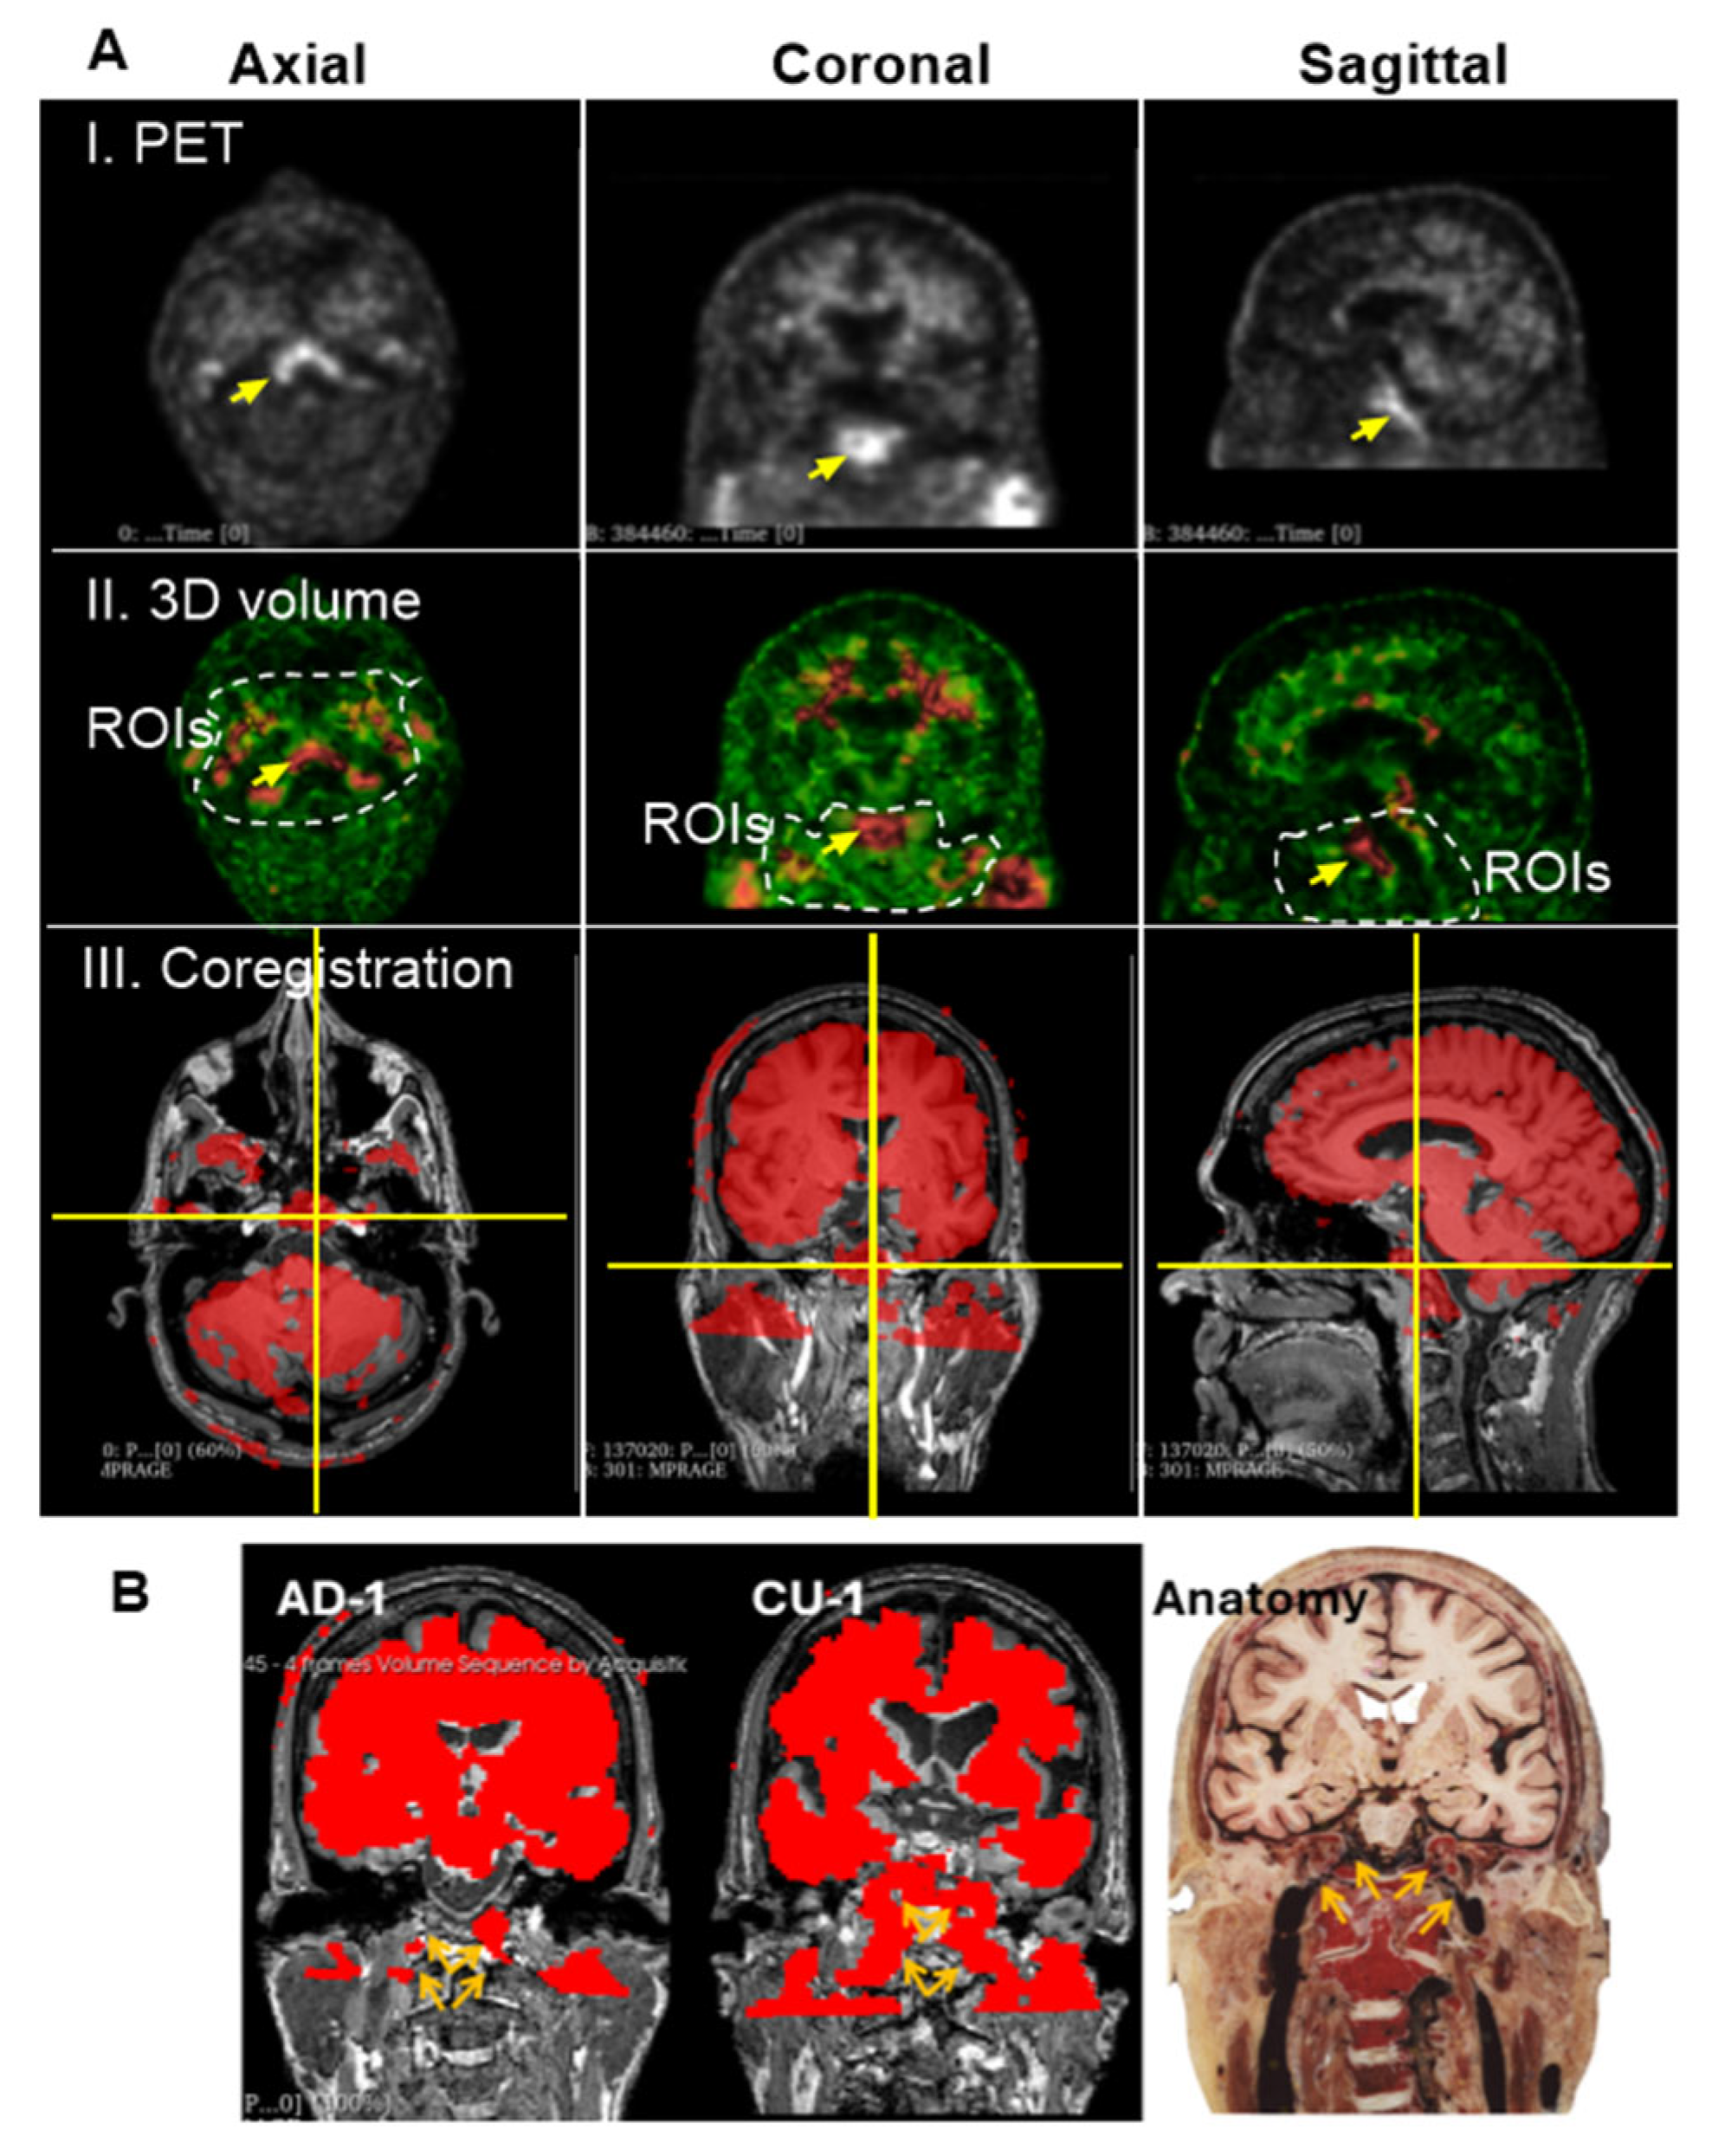

3.3. Group 2: Extracranial Aβ Signals in the Skull

In raw PET imaging, Aβ signals are detectable in both the brain parenchyma and extracranial regions. However, extracranial signals have largely been overlooked and remain poorly characterized. To begin addressing this gap, we sought to understand the spatial relationship between extracranial Aβ deposits and anatomical structures of the head. This was achieved by co-registering PET images with MRI scans from the same individuals. Figure 4A presents an axial view of the co-registered images, revealing that extracranial Aβ deposits are spatially co-localized with the skull. This pattern of colocalization was consistently observed in the coronal (Figure 4B) and sagittal (Figure 4C) views. These findings suggest that PET signals in superior regions are anatomically associated with the skull, rather than with meningeal structures.

Next, we investigated whether Aβ signals in the superior skull region exhibited organized patterns or were randomly distributed, as typically seen with plaque deposition. We observed that Aβ concentrations in the skull were lower than those in the brain parenchyma, as indicated by green coloration on the intensity scale. To isolate Aβ signals in the skull, we carefully defined ROIs in the superior regions, explicitly excluding cranial Aβ signals from the axial, coronal, and sagittal planes of the brain parenchyma.

Figure 5A illustrates a representative ROI selection strategy, with imaging dimensions of 52 slices in the anteroposterior (AP) direction, 47 slices in the right-left (RL) direction, and 3 slices in the inferior-superior (IS) direction. Figure 5B displays this extracranial ROI, finding that Aβ signals were spatially organized into distinct network-like patterns across the superior skull. Interestingly, these signals were not densely clustered as in the cranial regions. Several areas as labeled a, b, c, and d in the 3D visualization, showed no detectable Aβ signal. Due to the low concentration, the contrast against the black background was dim, making visualization challenging. To enhance clarity, the images were reprocessed using Fiji ImageJ (Figure 5B(II)), which improved the visibility of both the canal-like networks and the Aβ-free regions. In conclusion, low concentrations of Aβ were detected in the skull, forming organized canal-like networks that extended across the observed regions.

Figure 4. PET/MRI Coregistration. Representative MRI (left top panels) and PET scans (left bottom panels) from the CU-3 individual. Coregistration was conducted with 3D Slicer to set PET as the moving image (blue-green right panels) and MRI as the fixed reference (dark-gray right panels). Anatomical regions identified on MRI include a—Skull, b—Central nervous system (CNS), c—Subarachnoid space (SS), d—Meninges. Corresponding regions identified on PET include 1—extracranial Aβ signal, 2—CNS signal, 3—SS signal. Subpanels: (A) Axial view, (B) Coronal view, (C) Sagittal view. Extracranial Aβ signals are spatially aligned with the skull, not the meningeal regions.